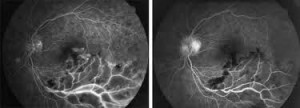

En este blog presentamos los resultados de dos años de tratamiento con bevacizumab intravítreo para el edema macular secundario a oclusión de rama venosa retiniana.

Se caracteriza por una intensa hiperemia y edema macular marcado, venas turgentes, dilatadas, tortuosas de color oscuro y de numerosas hemorragias en llama dispuestas radialmente en torno a la cabeza de la papila óptica y a lo largo del curso venoso ( como en un castillo de fuegos artificiales ).

En un estudio reciente se presentan los resultados tras un TRATAMIENTO de 2 años con bevacizumab intravítreo para el edema macular secundario a oclusión de rama central

CONCLUSION. Bevacizumab ofrece beneficios sustanciales a largo plazo en el tratamiento del Edema Macular secundario a una trombosis de la rama central de la retina.